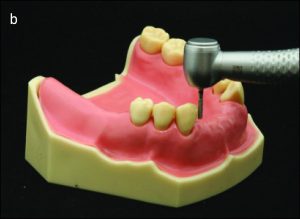

Throughout the mouth preparation process, the diagnostic model should be with the dentist on the analyzer table, positioned at the appropriate inclination to the path of insertion. Thus, the relationship between the diamond bur and the tooth surface to be shaped is projected from the model into the mouth (Figure 10-18).

b) Preparation made by projecting the relationship between the bur and the model into the patient's mouth.

The lingual and proximal surfaces of the teeth are prepped to serve as the guide planes, which have to be parallel to one another and to the prosthesis’s path of insertion. The position of the abutment teeth determines how the guide plane is prepared, and a cylindrical diamond or carbide bur is typically utilized (Fig. 10-19).